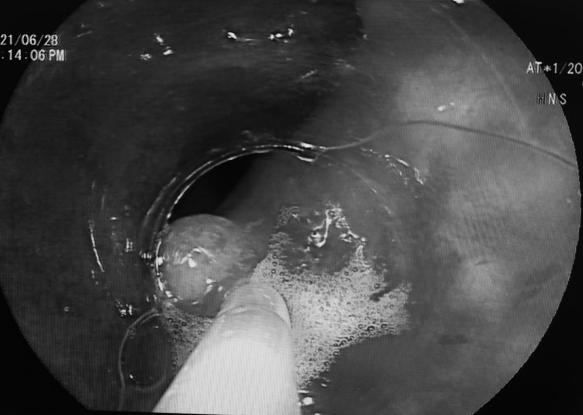

谢正元教授团队术前细评估并制定了相应的内镜下治疗策略,选择聚多卡醇制作泡沫硬化剂行内镜下直肠畸形静脉的止血治疗。4ml聚多卡醇原液 , 制成20ml乳白色微细泡沫硬化剂。术前确定好穿刺位置,选择出血明显的3个穿刺点,进行粘膜下及畸形血管内注射,当即出血停止。本次内镜下手术治疗在团队的默契配合下历时半个小时,手术非常成功,患者安返病房,次日出院。随访半月患者一般状况良好。

患者术前和术后内镜对比

术后内镜下直肠曲张静脉